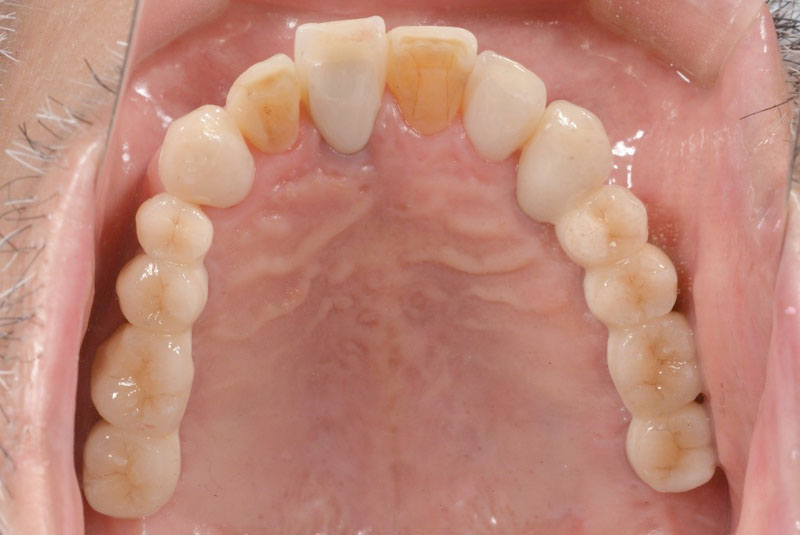

多数歯欠損のインプラント(サイナスリフト・GBR併用)

- 患者

- 50代男性

- 主訴

- インプラントができないかどうか相談。

できるだけきれいにしたい。

- 治療経過

- 前医にて上顎部分入れ歯を装着、下顎の奥歯を抜歯した状態で来院されました。また下顎の両側の臼歯の抜歯が必要と診断されたとのことでした。前医にインプラントを相談したが下顎はできるが、上顎は骨がないことを理由にインプラント不可能と診断され当院受診されました。診断の結果、下顎臼歯は保存可能、上顎臼歯部は左右上顎洞に対する骨造成(サイナスリフト)、前歯部はGBRにて骨造成を行い、インプラント埋入を行いました。

サイナスリフトはかなり専門性の高い外科処置であるため対応できる歯科医師は限られます。そのためショートインプラントや傾斜埋入で対応されることも多いですが、患者さんの年齢や希望を伺いながら当院では必要であれば積極的に行っております。その他不良補綴物の除去、根管治療、虫歯治療を行い全顎に対して審美的修復を行い治療終了までに2年を要しました。ちなみに当院では1本も抜歯は行いませんでした。保存できる歯と抜歯の必要な歯をしっかり診断することも必要です。